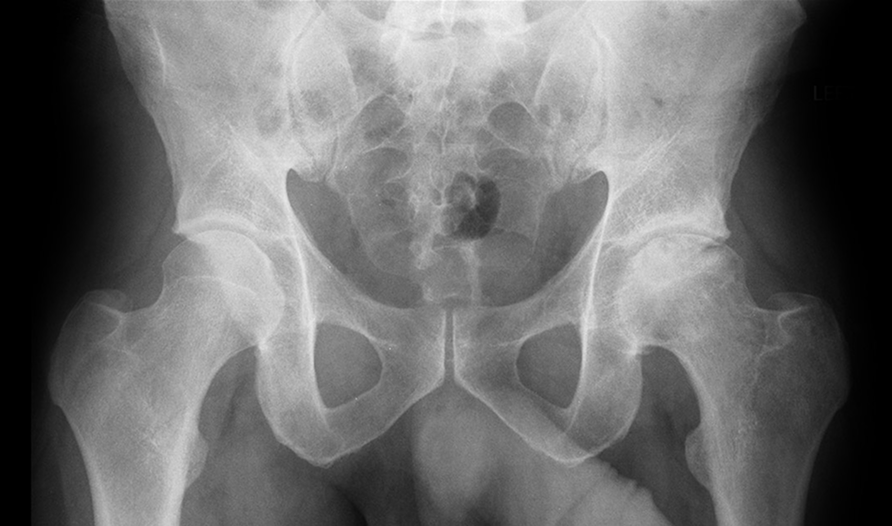

Analysing Hip Dysplasia and Impingement on X-rays

RBhip™ is able to identify key measurements needed for hip dysplasia diagnosis